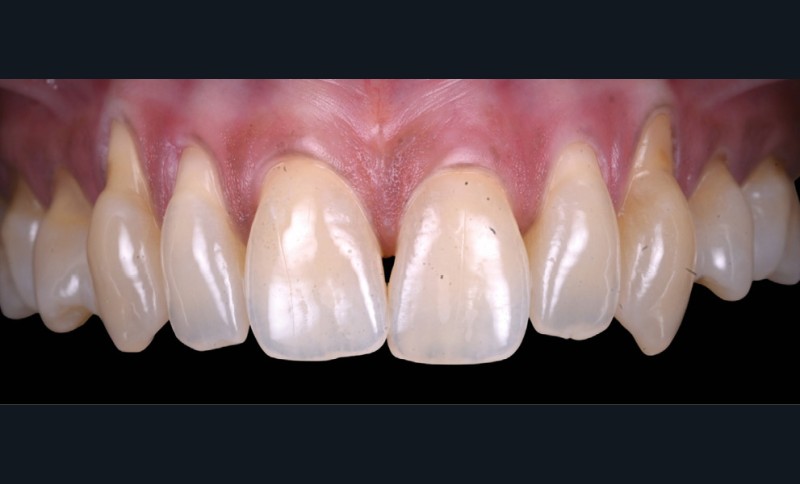

L’examen clinique révèle des récessions gingivales généralisées au maxillaire (fig. 1), de type RT1 et RT2 selon Cairo, responsables d’une hypersensibilité dentinaire marquée.